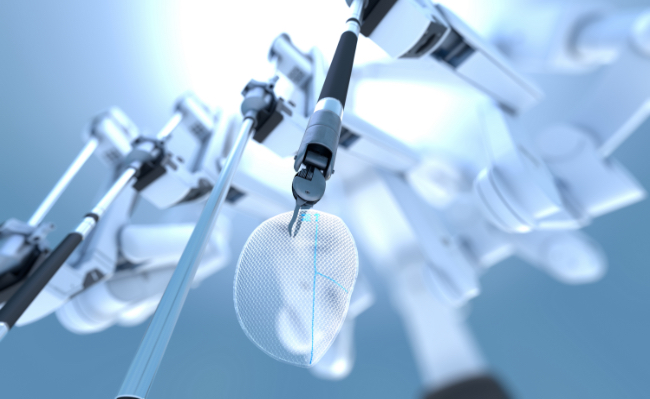

Fill out the form below to learn how our surgical business continues to innovate products that help empower surgeons to choose the right product, for the right procedure, for the right patient.